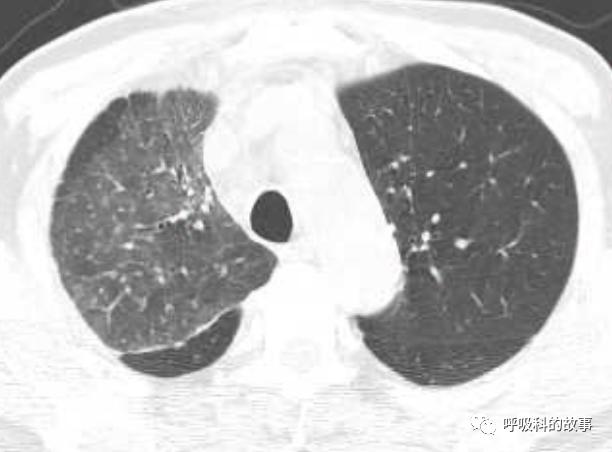

所以如果我们能对这些特征有所了解,那么其实诊断肺马尔尼菲蓝状菌感染并不是什么难事。后来我们又遇到一个肺部结节的患者(如下图):

大家可以发现这个小结节外周有晕征,内部有一小空洞,更重要的是纵隔淋巴结肿大,因此我们马上考虑到肺马尔尼菲蓝状菌感染,进行气管镜检查,做纵隔淋巴结穿刺培养出马尔尼菲蓝状菌。